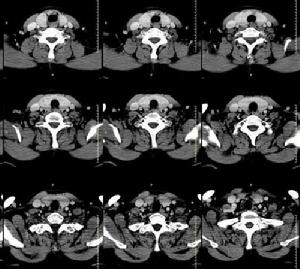

雙側甲狀腺腫大 - CT病例3.功能亢進性腺瘤:合併有功能亢進症狀者,稱功能亢進性腺瘤,亦稱毒性腺瘤,此種腺瘤發生惡變的可能性較小。